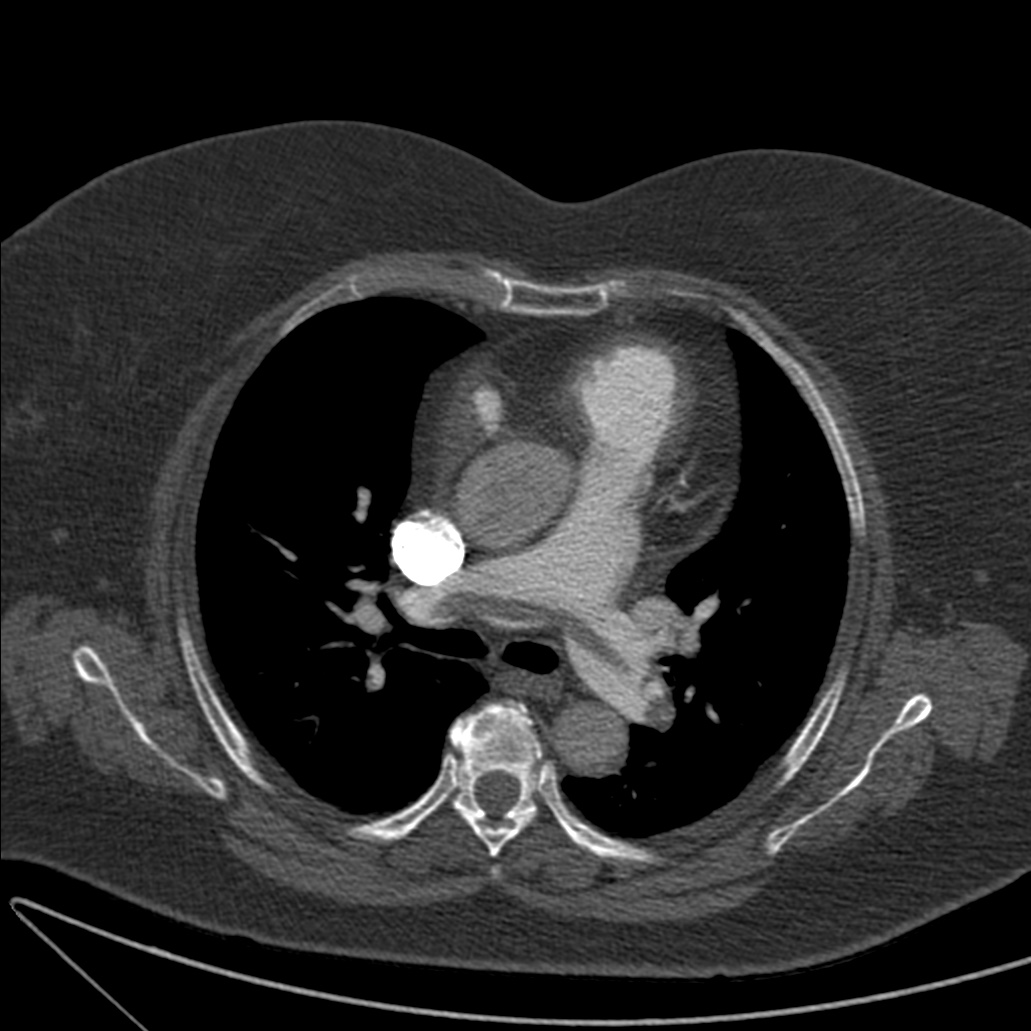

Obstrucción por trombo de la arteria pulmonar principal derecha.

Signo del Cono o Cucurucho en un corte perpendicular del vaso, sugestivo de TEP agudo.